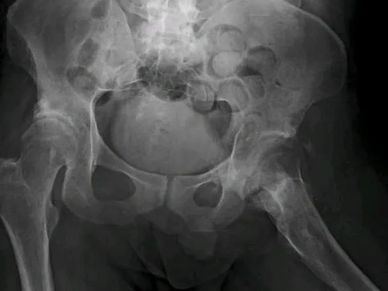

Mirá cómo recuperamos la movilidad en un caso de artrosis severa y deformidad acetabular mediante tecnología 3D de alta precisión. Planificación preoperatoria en 3D para cirugía de cadera con artrosis severa e importante deformidad acetabular. Se imprimieron biomodelos en 3D y guías para la correcta colocación de los componentes protésicos. De esta manera, se logró restaurar la longitud de las piernas y se eliminó el dolor invalidante que presentaba el paciente.

Paciente con artrosis severa y deformidad ósea que dificultaba la colocación acetabular. Con tomografía realizamos planificación 3D y diseñamos una guía quirúrgica personalizada impresa en 3D. En quirófano replicamos el plan: posicionamiento preciso del componente y restauración del centro de rotación. La tecnología 3D aporta más precisión, seguridad y predictibilidad en casos complejos.